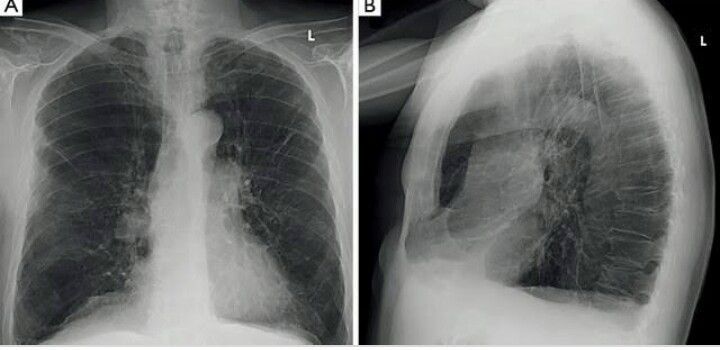

Chronic Obstructive Lung Disease is most commonly found in people with a long history of smoking. During acute exacerbations they present with Shortness of breath, increased respiratory rate, increased cough, tachypnea and etc On Chest X-ray findings are bilaterally hyperlucent lungs, flattened hemidiaphragm, widened costophrenic angles, horizontal ribs and narrow mediatinum.